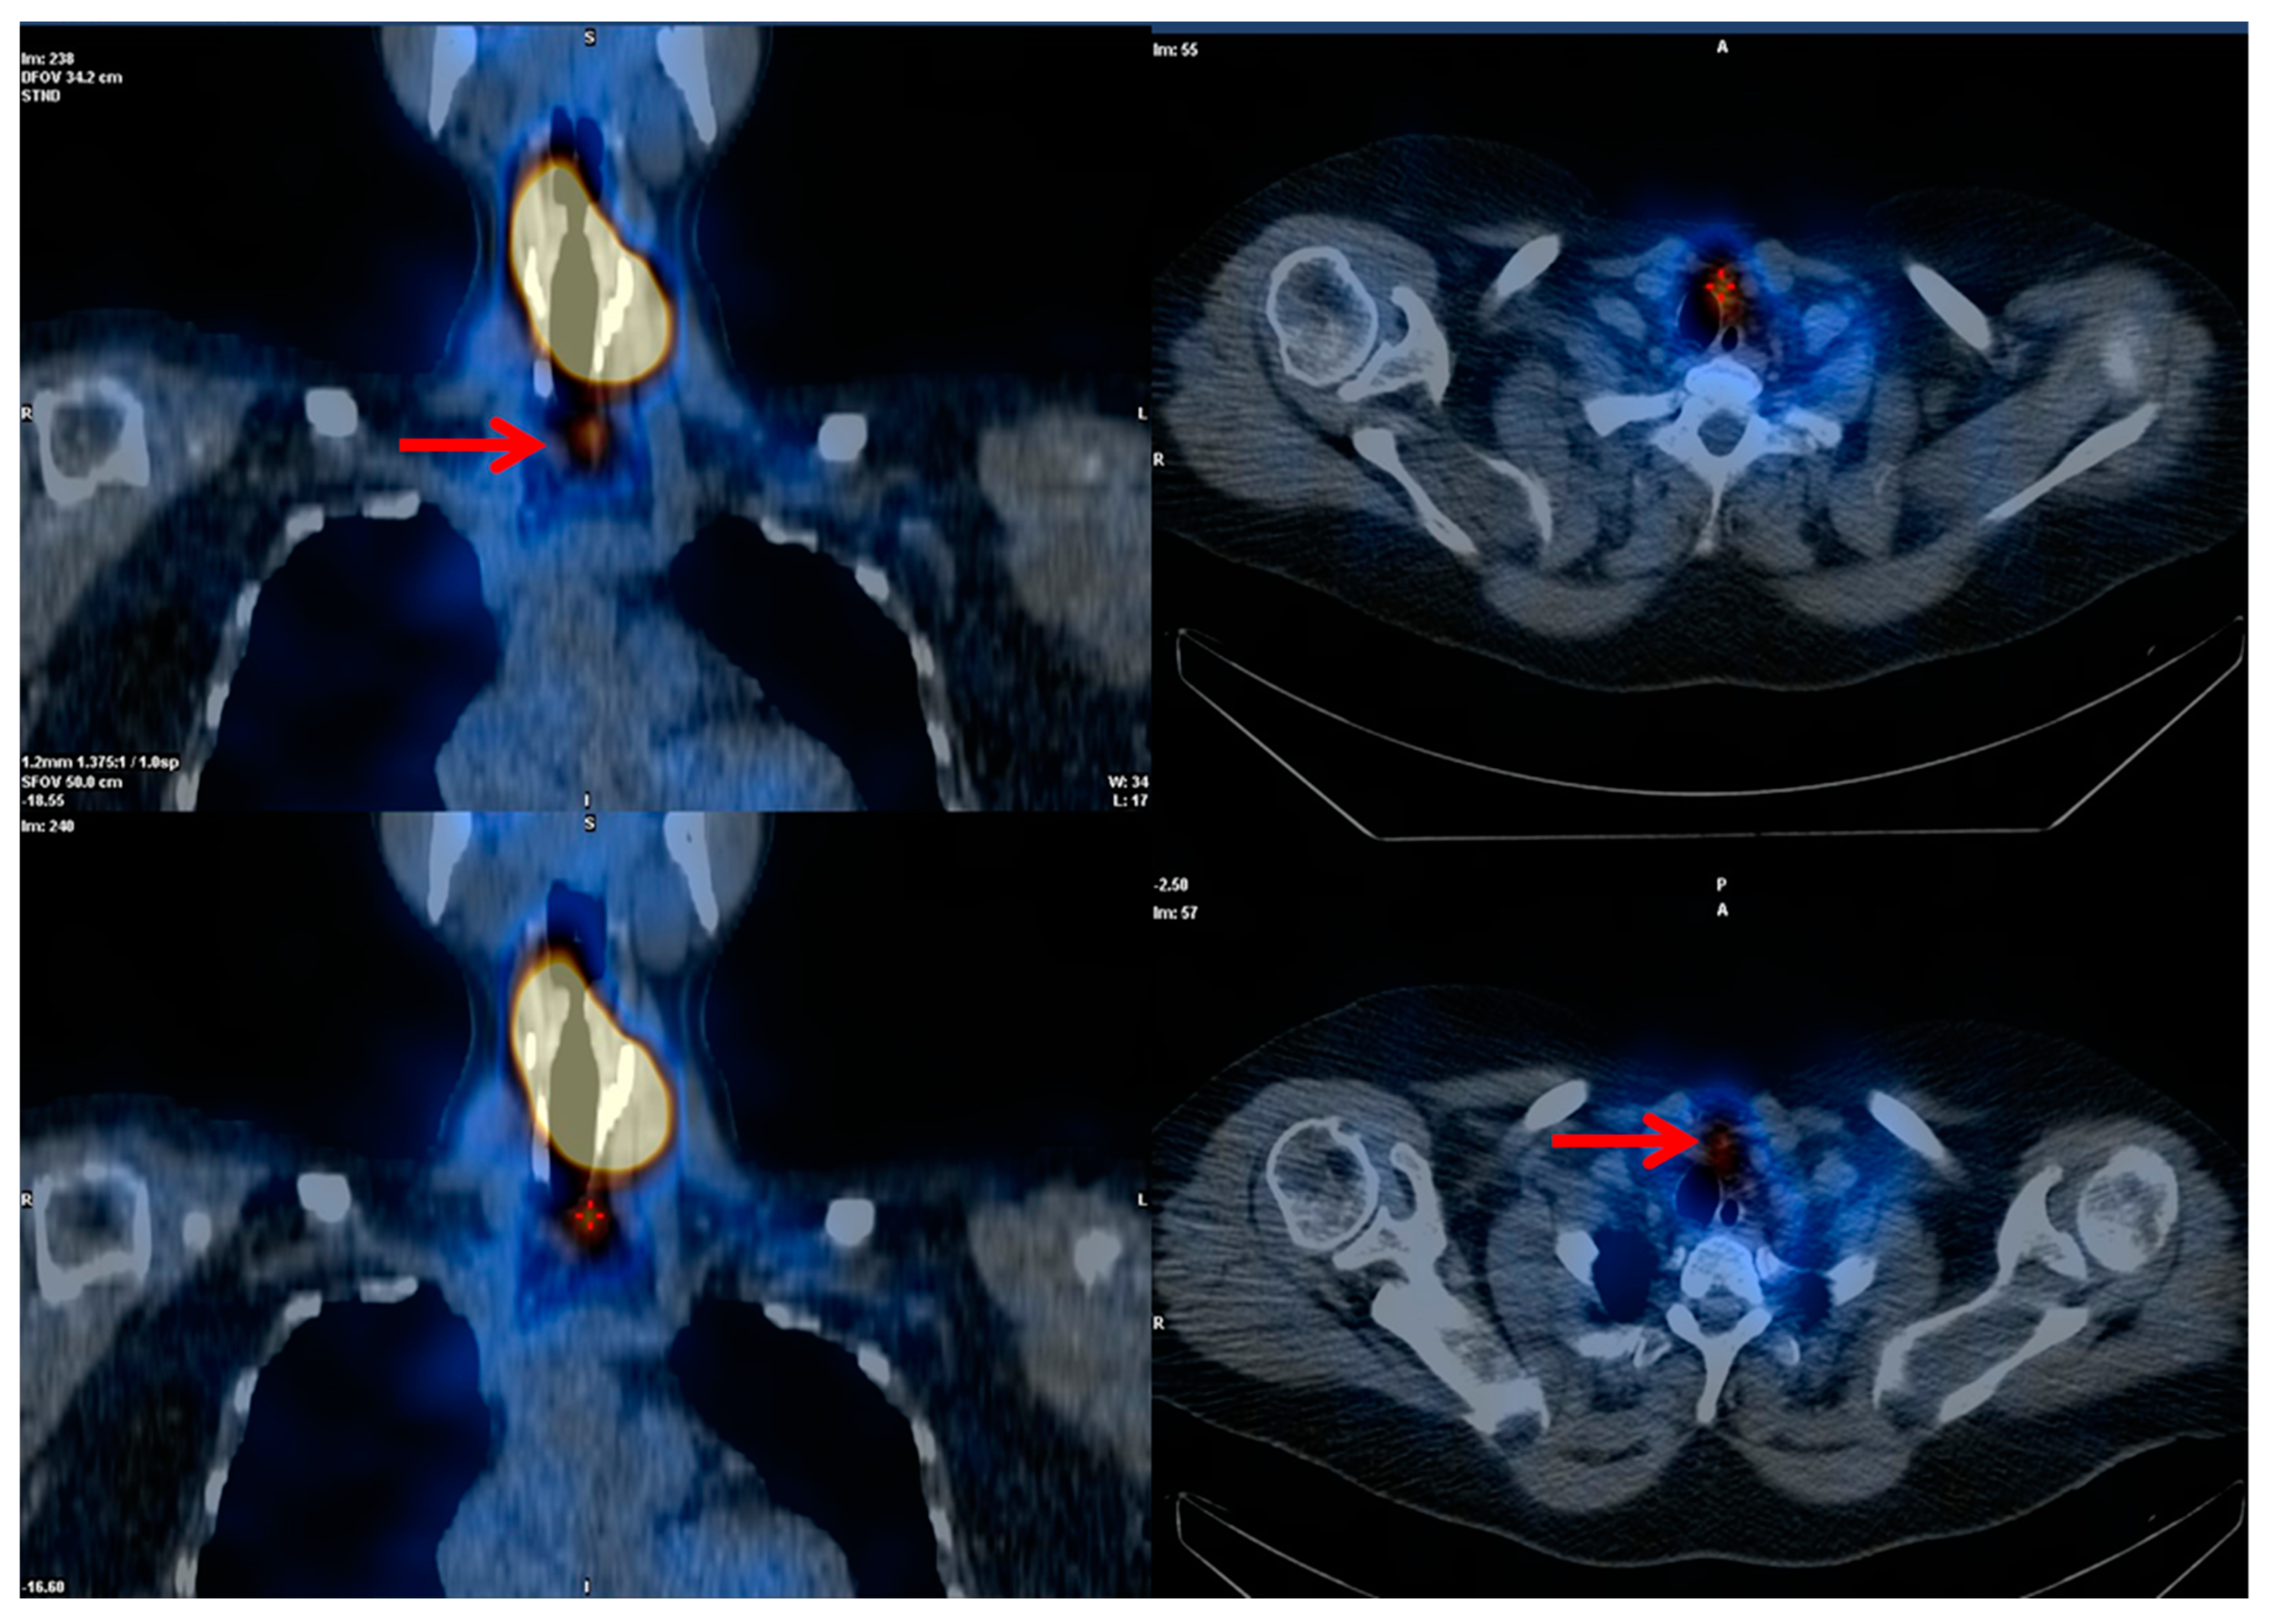

7.3. Molecular Imaging and Theragnostics